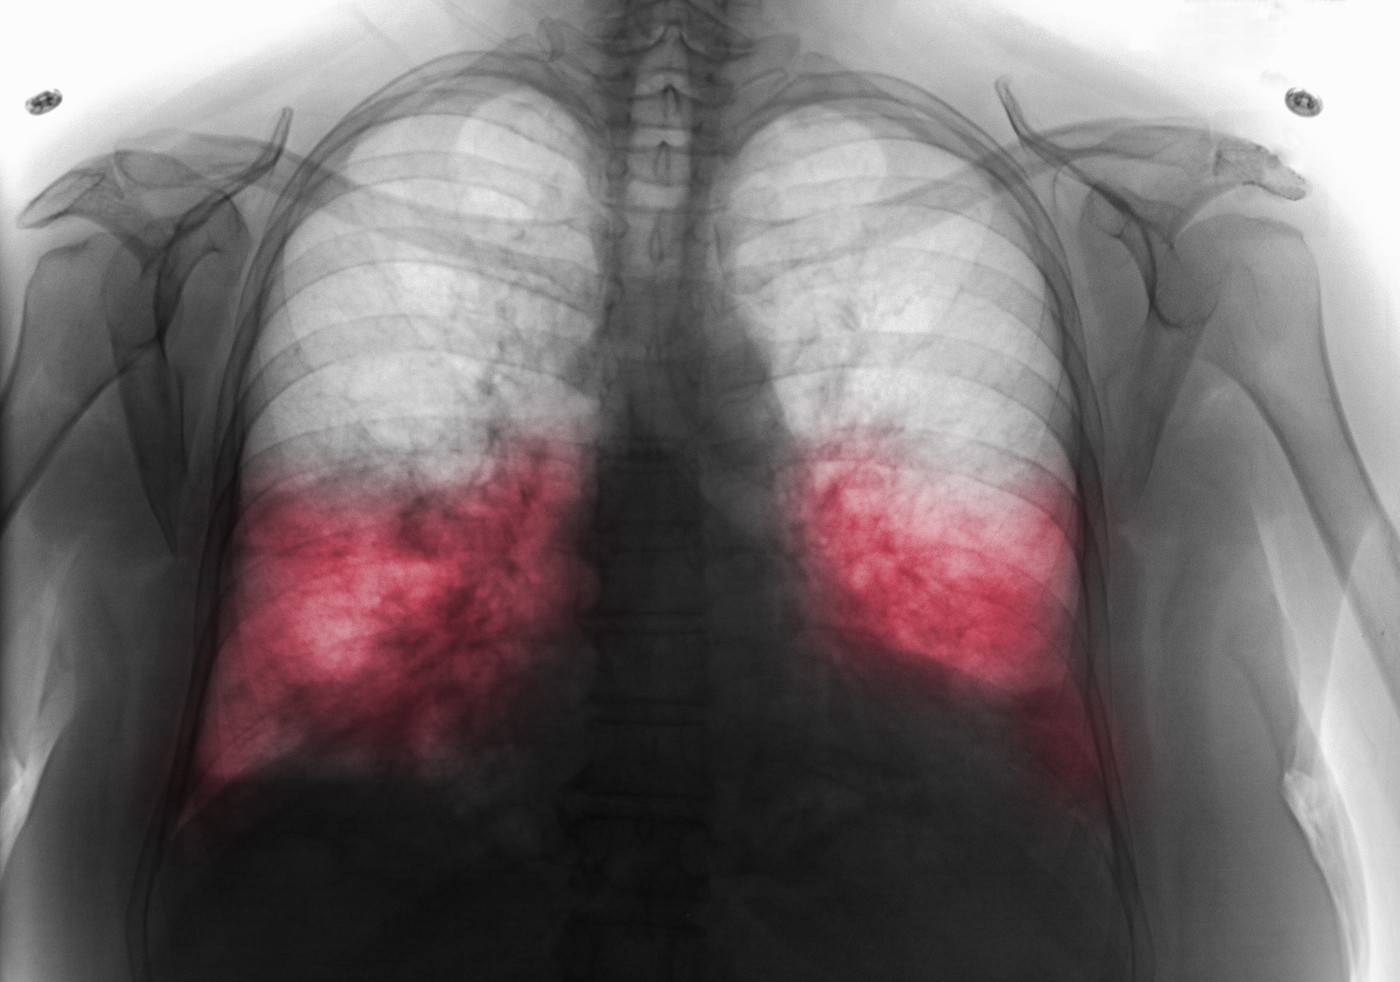

Simptomi hodajuće upale pluća Foto: Callista Images / ImageSource / Profimedia Simptomi hodajuće upale pluća Foto: Callista Images / ImageSource / Profimedia Simptomi hodajuće upale pluća Foto: Callista Images / ImageSource / Profimedia Raste broj zaraženih hodajućom upalom pluća: Ako imate ove simptome treba da se odmah javite lekaru autor: Milorad Milovanović Zdravlje 27. nov. 2024. 10:00 6 Podeli vest: Hodajuća upala pluća, poznata i kao atipična pneumonija, predstavlja oblik infekcije pluća koji se često javlja sa blažim simptomima u poređenju sa klasičnom upalom pluća. Zbog toga mnogi ljudi nastavljaju sa svojim svakodnevnim obavezama ne shvatajući da su ozbiljno bolesni, što ovoj bolesti daje naziv "hodajuća". Podeli vest: Oglas Šta uzrokuje hodajuću upalu pluća? Ovu vrstu infekcije najčešće izaziva bakterija Mycoplasma pneumoniae. Za razliku od drugih oblika upale pluća, simptomi se razvijaju postepeno, obično tokom nekoliko dana ili čak nedelja. Bolest se lako prenosi kapljičnim putem, poput kijanja ili kašljanja, što je čini čestom u zatvorenim prostorima, poput škola, kancelarija ili porodica. Simptomi na koje treba obratiti pažnju Simptomi hodajuće upale pluća često su blagi, ali mogu trajati nedeljama ako se ne leče. Najčešći simptomi uključuju: Suv kašalj koji se pogoršava tokom vremena.Blaga do umerena temperatura, često praćena drhtavicom.Umor i slabost koji ometaju svakodnevne aktivnosti.Bol u grlu ili osećaj grebanja pri gutanju.Blagi bol u grudima ili nelagodnost prilikom disanja.Glavobolja i povremena vrtoglavica. Kod nekih osoba mogu se javiti i simptomi nalik gripu, poput bolova u mišićima i zglobovima. Zbog sličnosti sa prehladom ili virusnim infekcijama, bolest se često ne prepoznaje odmah. Ko je najugroženiji? Hodajuća upala pluća može pogoditi ljude svih uzrasta, ali najčešće pogađa: Decu i tinejdžere, posebno u školskim kolektivima.Odrasle koji rade u zatvorenim prostorima sa velikim brojem ljudi.Osobe sa oslabljenim imunitetom ili hroničnim bolestima. Kako se postavlja dijagnoza? Lekar obično postavlja dijagnozu na osnovu pregleda simptoma, ali se ponekad preporučuju dodatni testovi, poput rendgena pluća ili analiza krvi, kako bi se isključili drugi oblici upale pluća. Lečenje i oporavak Hodajuća upala pluća se uglavnom leči antibioticima koje prepisuje lekar. Uz adekvatnu terapiju, simptomi se povlače za nekoliko dana, ali umor i slabost mogu trajati duže. Važno je pridržavati se saveta lekara i završiti terapiju, čak i ako se osećate bolje nakon nekoliko dana. Tokom oporavka, preporučuje se: Održavanje hidratacije unošenjem dovoljne količine tečnosti.Odmaranje i izbegavanje fizičkih napora.Unošenje hranljivih obroka bogatih vitaminima. Prevencija: Kako se zaštititi? Prevencija hodajuće upale pluća je ključna, posebno u sezonama kada se respiratorne infekcije češće javljaju. Neki od najvažnijih koraka uključuju: Redovno pranje ruku toplom vodom i sapunom, posebno nakon boravka u javnim prostorima.Izbegavanje bliskog kontakta sa zaraženim osobama.Jačanje imuniteta pravilnom ishranom, fizičkom aktivnošću i dovoljnim snom.Vakcinacija protiv sezonskog gripa, jer grip može povećati rizik od sekundarnih infekcija. Iako hodajuća upala pluća ne zahteva uvek hospitalizaciju, ne treba je olako shvatiti. Blagi simptomi mogu zavarati i dovesti do kasnog lečenja, što povećava rizik od komplikacija. Ako primetite simptome koji traju duže od nedelju dana ili se pogoršavaju, obavezno se obratite lekaru. Pravovremena dijagnoza i lečenje ključni su za brz i potpuni oporavak. Lekar opšte prakse otkriva koja 3 vitamina treba da se obavezno piju tokom zime: "Bolje da ih uzmate, nego da se lečite" Zdravlje 9 Zimi najviše treba jesti ove hrane jer je bomba za imunitet: Srbi je obožavaju i mnogo je zdravija nego što mnogi misle Zdravlje 11 simptomi upala pluća Pratite nas na društvenim mrežama: Koje je tvoje mišljenje o ovoj temi? Učestvuj u diskusiji ili pročitaj komentare Budite prvi koji će ostaviti komentar Pošalji komentar Pročitaj komentare (6)